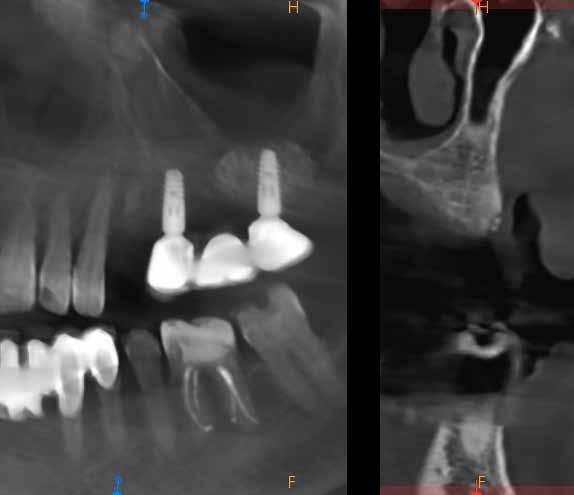

A korai harmicas éveiben járó hölgy rendelőnkbe érkezésének oka a jobb felső nagymetsző fog bizonytalan érzkenysége, elmondása alapján gyermekkorában trauma érte a felső frontrégiót. A frakturált klinikai koronákat kompozittöméssel helyreállították, egyéb kezelést akkor nem tartottak szükségesnek. Az utóbbi hónapokban tapasztalt érzékenység miatt kereste fel rendelőnket. A klinikai vizsgálat (1. és 2. kép) és a CBCT felvétel (3. kép) alapján diagnosztizált külső gyökérreszorpció megoldására a fog eltávolítását, implantátum

bukkális 1. kép: Kiindulási állapot, 2020. január. 3. kép: Kiindulási CBCT felvétel. 2. kép: Kiindulási állapot a palatinális oldal felől.

1. ábra: Megfelelő szájhigiénia – panorámaröntgen. 2. ábra: A 2.5, 2.6 és 2.7-nek megfelelő terület a röntgenfelvételen.

és jelentős mobilitással rendelkezett. A radiológiai vizsgálat után egyértelműen látszódott, hogy a fogon még nem végeztek gyökérkezelést. A 2.6-os és 2.7-es fogaknak megfelelő területen az arcüreg kiterjedése jelentős volt, vertikális csontmennyiség szignifikánsan csökkent (1. és 2. ábra).